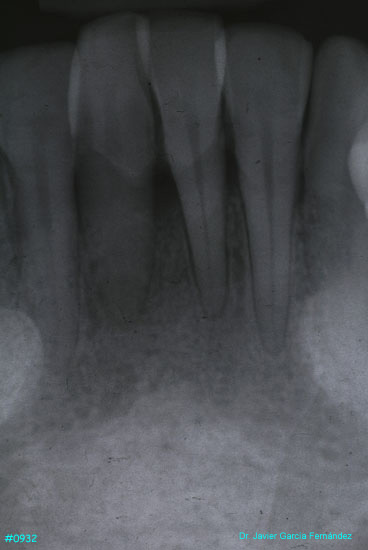

Atlas of Surgical Techniques in Periodontics. Chapter III. Atlas de Técnicas Quirúrgicas en Periodoncia